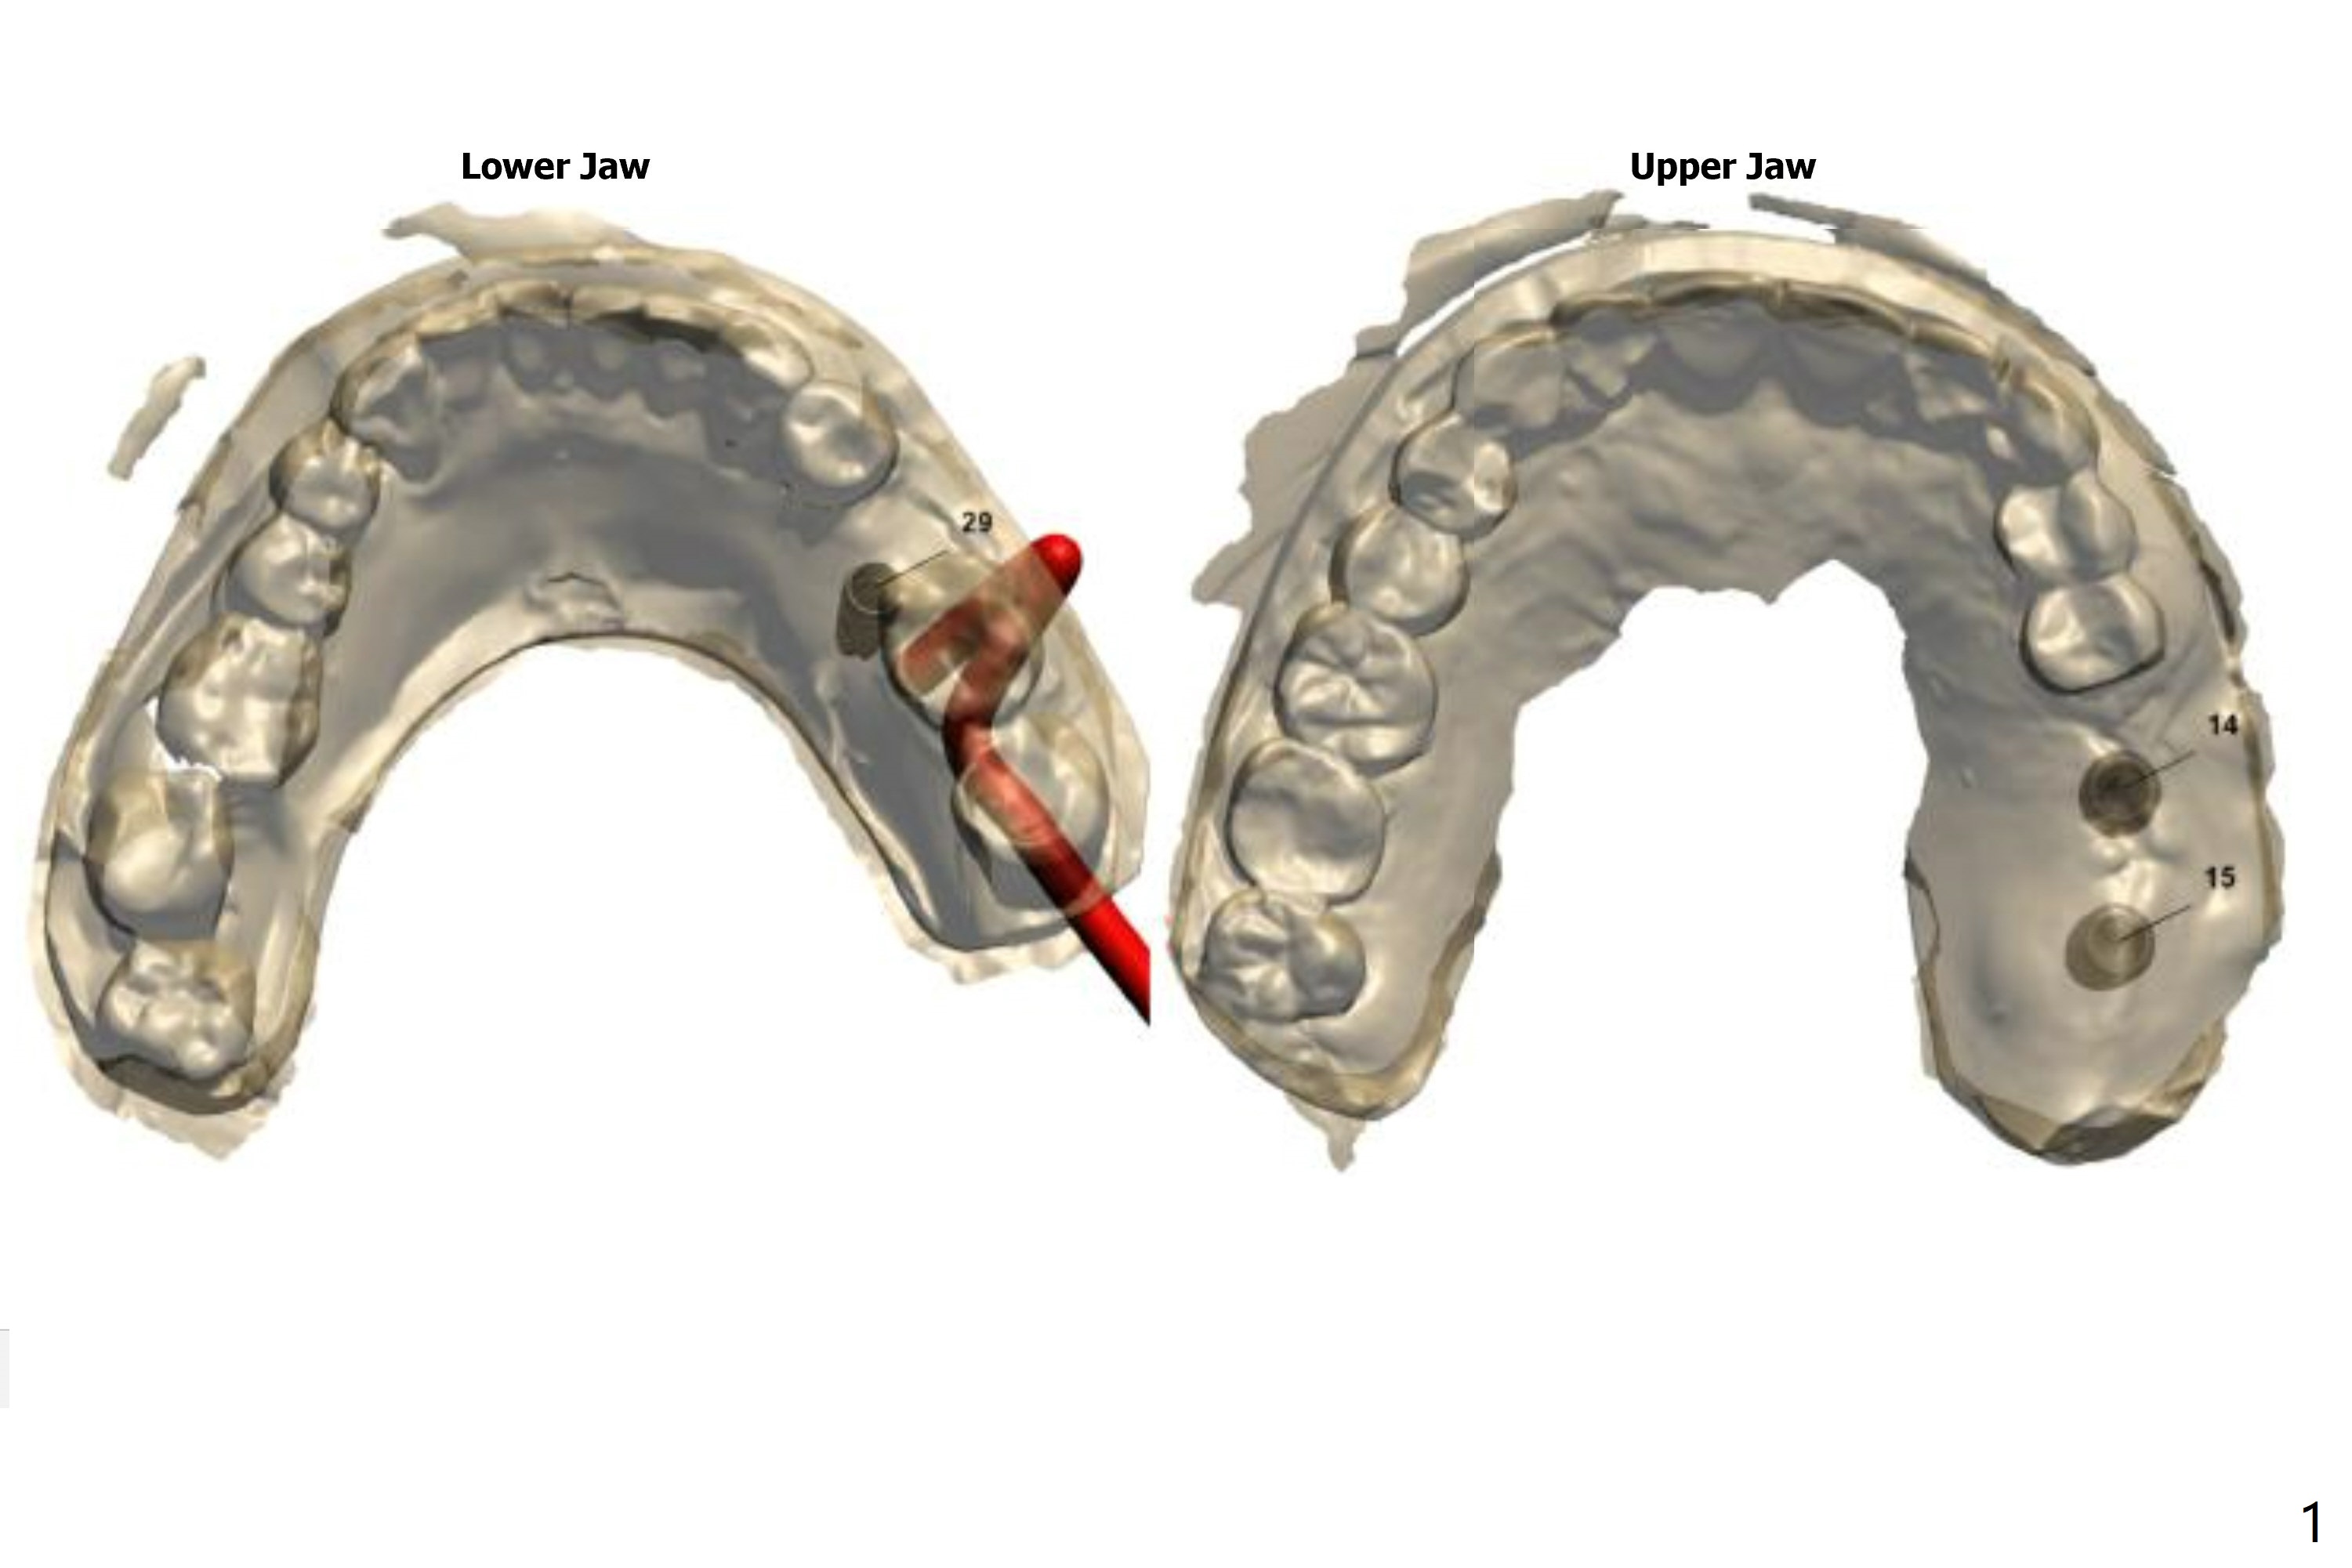

Return to Upper Molar Lower Premolar Immediate Implant, Trajectory